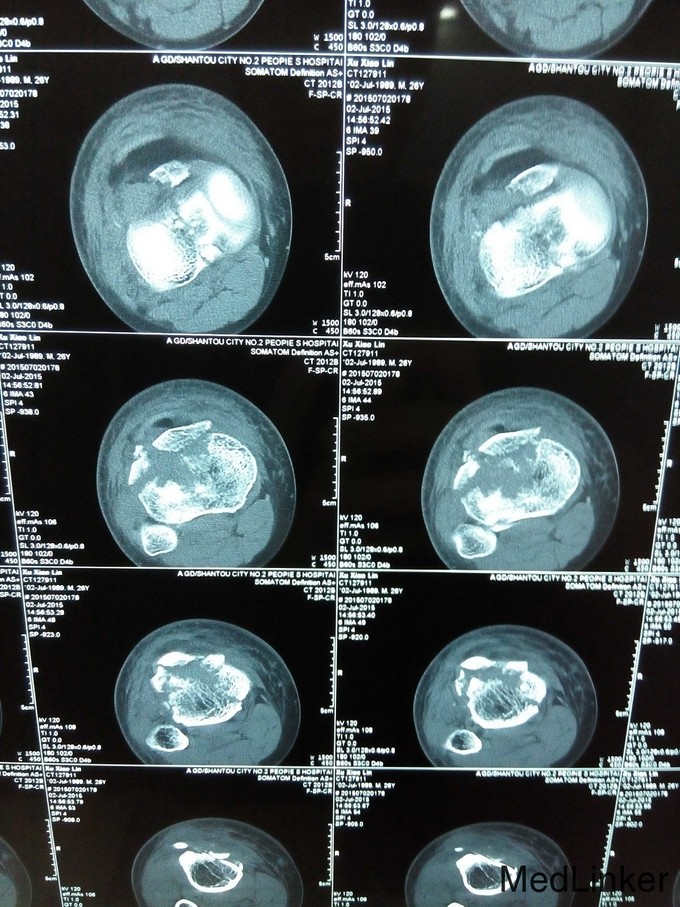

患者,男性,26岁,车祸伤2小时于2015-7-2入院。

右膝高度肿胀,压痛,胫骨结节外侧皮肤擦伤,胫骨外髁有骨檫感,关节活动功能障碍,右踇趾背伸功能减退,足趾感觉无障碍,足背动脉搏动稍弱,右下肢纵轴叩击痛(+)。右膝关节X线及CT检查示:右胫骨平台粉碎性骨折,内外髁骨折并累及关节面,右膝关节MRI检查示外侧半月板损伤,交叉韧带及内侧半月板无明显损伤。

右胫骨平台粉碎性骨折(内外髁骨折) 入院后予跟骨骨牵引,一周后硬外麻下行胫骨平台骨折切开复位内固定术,术后伤口拆线痊愈出院。

胫骨平台骨折分6型,患者内外髁骨折,属第6型,手术采用内外侧切口钢板固定植骨术,该患者胫骨结节撕脱性骨折,故术中加用两条克氏针(螺丝无把持力)。请各位前辈赐教。